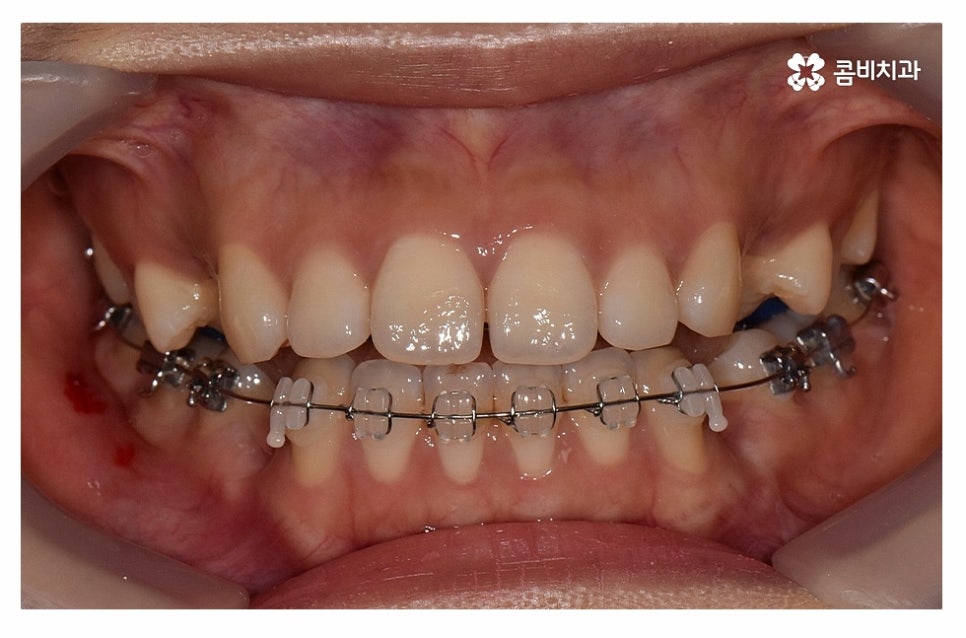

윗니는 설측교정으로 진행하고 아랫니는 일반적인 순측교정으로

치료를 진행하는 방식을 콤비교정이라고 부르고 있는데요.

보통 평소에 대화를 하고 웃을 때 윗니가 위주로 보이기 때문에

콤비교정은 심미적인 치료 방법이며 혀가 위치한 아랫니는

순측교정을 하기 때문에 발음상의 불리함이나 이물감 등에서

유리하기 때문에 합리적인 치료 방법이라고 할 수 있어요.